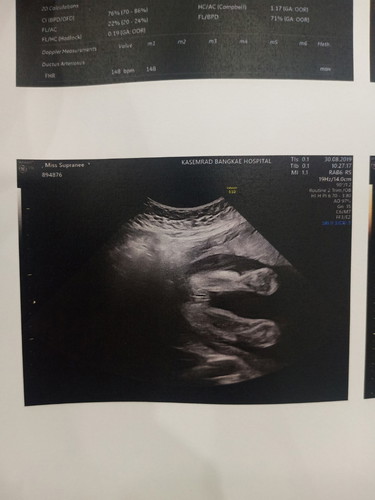

ซาวมาเมื่อเช้าค่ะได้ลูกสาว ดีใจสุดๆไปเลย?

25สัปดาค่ะ

ชัดมากเลยคะแม่